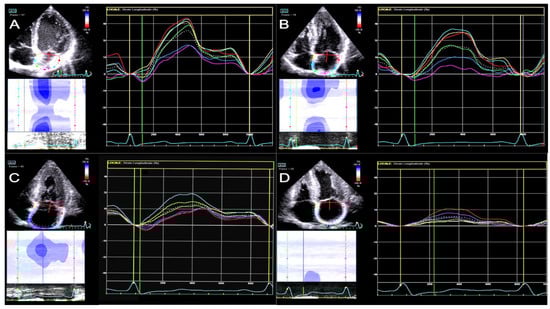

All atrial strain parameters were significantly impaired in CA patients than in Co (p < 0.001 for all three comparisons) (See Table 2 and Figure 2).

Therefore, to differentiate and exclude patients with reduced EF, who exhibited more altered parameters potentially linked to heart failure with systolic dysfunction and its hemodynamic consequences, we decided to compare the CApEF group with the HCM group. On comparing the CApEF group with the HCM group, we found a significant difference in EF (p = 0.004), E/e’ ratio, s’ wave, and TAPSE. The LAS-reservoir, LAS-conduit, and LAS-contraction values were numerically lower in the CApEF group compared to the HCM group (although without statistical significance) (Table 3 and Figure 3).

Figure 2. LA strain curves in comparison between subjects from the four groups. (A)—Co subject; (B)—HCM patient; (C)—CApEF patient; (D)—CArEF patient.